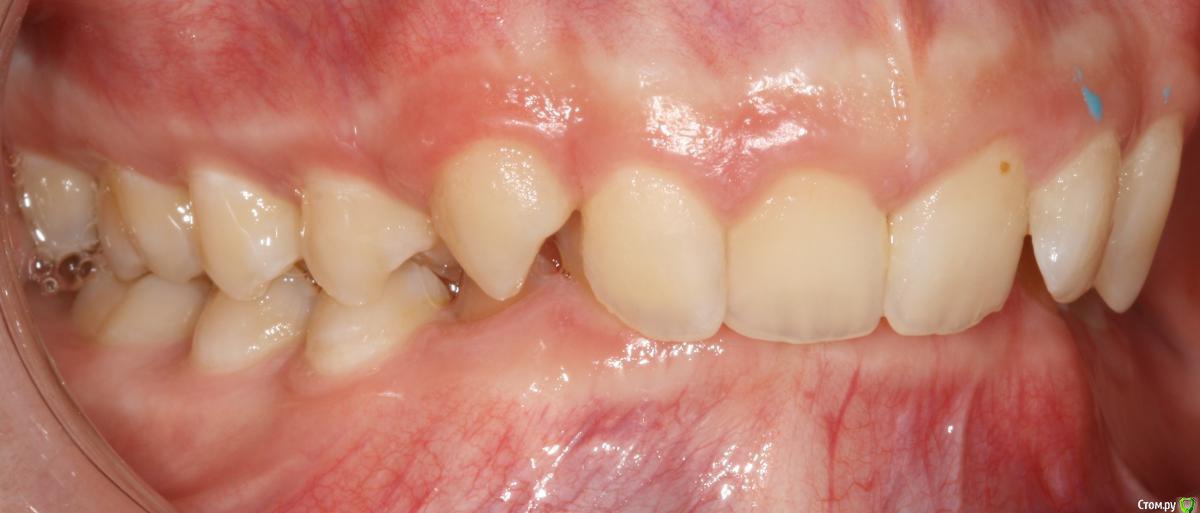

Opdihatop Опубликовано 24 октября, 2017 Поделиться Опубликовано 24 октября, 2017 И еще раз здравствуйте! Сразу хочу презентовать еще одного мальчика. Лично я такого еще не видел, а потому хочу понять, что тут делать. Думаю, невооруженным взглядом видно гипертонус и гиперплазию массетеров и гиперплазию углов н/ч из-за этого. Из-за чего это может быть и что тут делать? Как расслабить и что вообще делать с мышцами? Слать ли на сцинтиграфию (мало ли, может рост продолжается)? Есть ли шанс повысить прикус или такие мышцы все равно вколотят? Члх или нет? Заранее спасибо! Ссылка на комментарий

Brigita Опубликовано 24 октября, 2017 Поделиться Опубликовано 24 октября, 2017 (изменено) рост продолжается. по позвонкам можно посмотреть. даже не пик еще.а с мышцами... ну однозначно с какого то функционального аппарата начать надо... миомассаж редко где можно найти. да он и как припарка тут. Аппаратное расслабление если только. А вообще он на спортсмена похож, на футболиста. Изменено 24 октября, 2017 пользователем Brigita 1 Ссылка на комментарий

Brigita Опубликовано 25 октября, 2017 Поделиться Опубликовано 25 октября, 2017 (изменено) Может с эластопозиционера начать пока... Изменено 25 октября, 2017 пользователем Brigita Ссылка на комментарий

krokomot Опубликовано 25 октября, 2017 Поделиться Опубликовано 25 октября, 2017 Выкладывайте кт, сильно сомневаюсь что повышенный тонус массетер привел к гиперплазии углов. Перестройка да, гиперплазия нет. Ссылка на комментарий